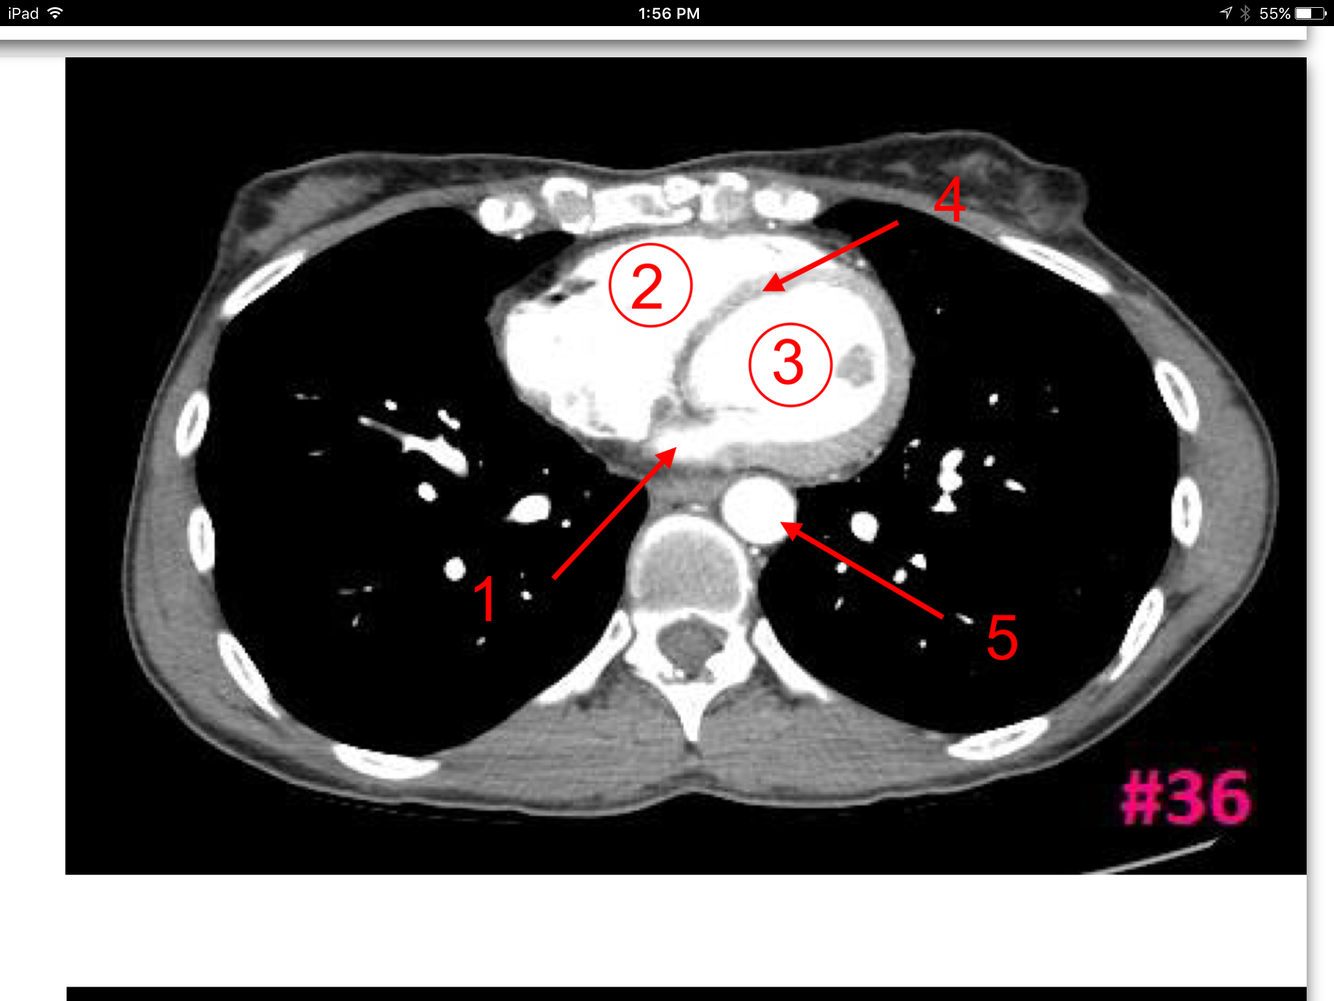

12

Q

A

Superior vena cava

Ascending aorta

Descending aorta

Trachea